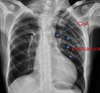

TEP

91

¿Qué es el signo de westermark?

Hiperlucencia periférica (por oligoemia)

92

Signo de Westermark = TEP

93

Dilatación de arteria pulmonar = TEP